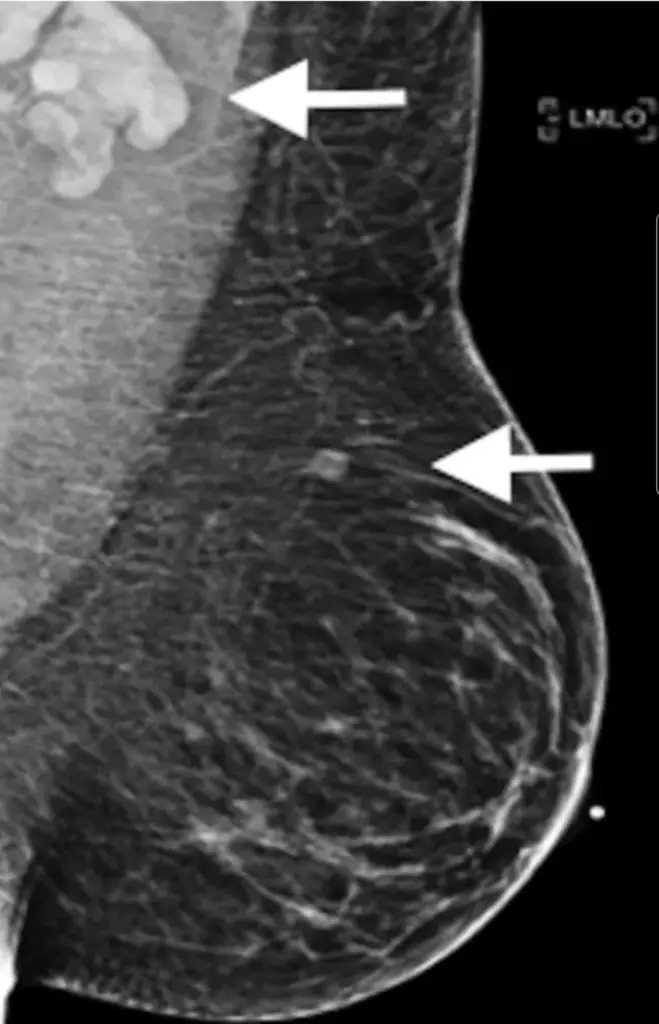

A study (read below) published by the Radiological Society of North America recently concluded vaccine-induced lymphadenopathy was an important side effect for clinicians, patients, and cancer researchers to be aware of as it could result in a false cancer diagnosis.

In Australia, women over 50 who require regular mammograms have been advised to either have a mammogram first, or delay it until six weeks after vaccination, to avoid any confusion.